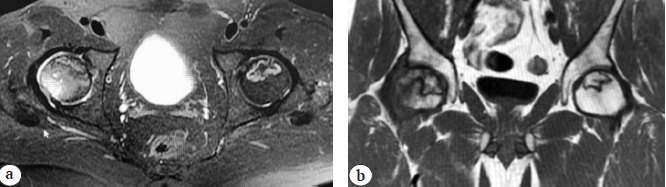

At 80 days after the disease onset, the patient noted severe pain in both hip joints (visual analog scale [VAS] 8 points) and lower back and therefore experienced significant difficulty in walking. Such symptoms were noted by the patient for the first time in his life. According to magnetic resonance imaging (MRI) performed 120 days after the COVID-19 onset, ARCO IIC bilateral osteonecrosis of the femoral heads was diagnosed on both sides (Fig. 1).

Fig. 1. MRI signs of bilateral femoral head osteonecrosis (ARCO IIC) in patient 1: a — axial view; b — frontal view